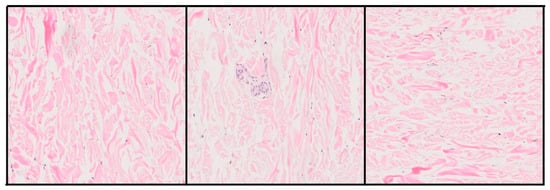

In this context, deep learning has proven especially promising. Models such as Convolutional Neural Networks (CNN) have reached performance levels comparable to those of human experts in tasks such as tumor classification, metastasis detection, and cellular structure segmentation [7,8]. In the case of melanoma, several studies have shown that it is possible to train classification models with H&E-stained images, achieving clinically relevant results, particularly when distinguishing malignant melanomas from melanocytic nevi (Figure 1)—the main diagnostic challenge in pigmented lesions [9].

Figure 1. Histological comparison between malignant melanoma (left) and melanocytic nevus (right), stained with H&E.